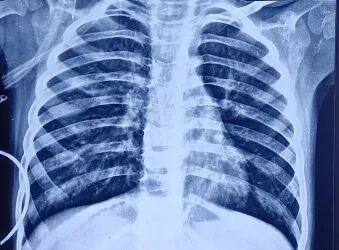

胸片显示双肺野过度充气,伴右肺中野不均匀浸润影及支气管壁增厚(图1)。胸部高分辨率CT扫描显示右肺上叶前段可见厚壁囊腔,可能存在交通,紧邻管壁明显增厚的亚段支气管——提示囊性支气管扩张(图2)。免疫功能缺陷检查已排除:HIV报告正常,免疫球蛋白谱正常,淋巴细胞亚群分析正常。IgA=54.67 mg/dL,IgG=990.32 mg/dL,IgM=404.186 mg/dL,IgE=16.3 IU/mL,CD3(T细胞)=2237.32 个/μL ,62.85% ;CD4 TH细胞=1165.21 个/μL ,32.73% ;CD8 T细胞=1065.26 个/μL,29.92%;CD4/CD8比值1.09,均处于正常范围

1.患者入院时胸片。显示双肺野过度充气,左肺中野不均匀密度增高影伴支气管周围增厚。